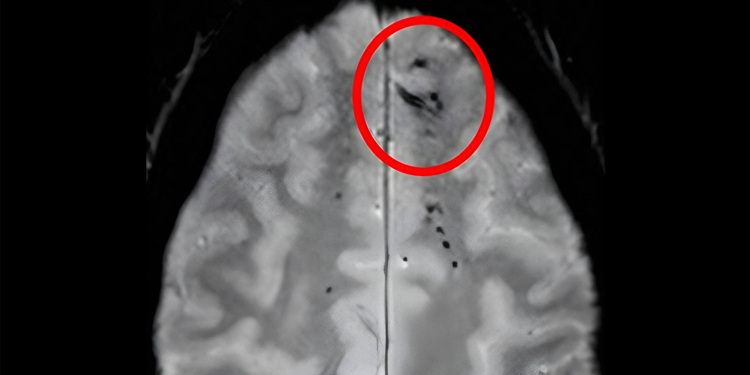

(MedPage Today) — The location and amount of brain microbleeds that a person has could be telling of their risk of dementia, according to an observational analysis.

Compared with controls with no cerebral microbleeds detected on MRI, there was…